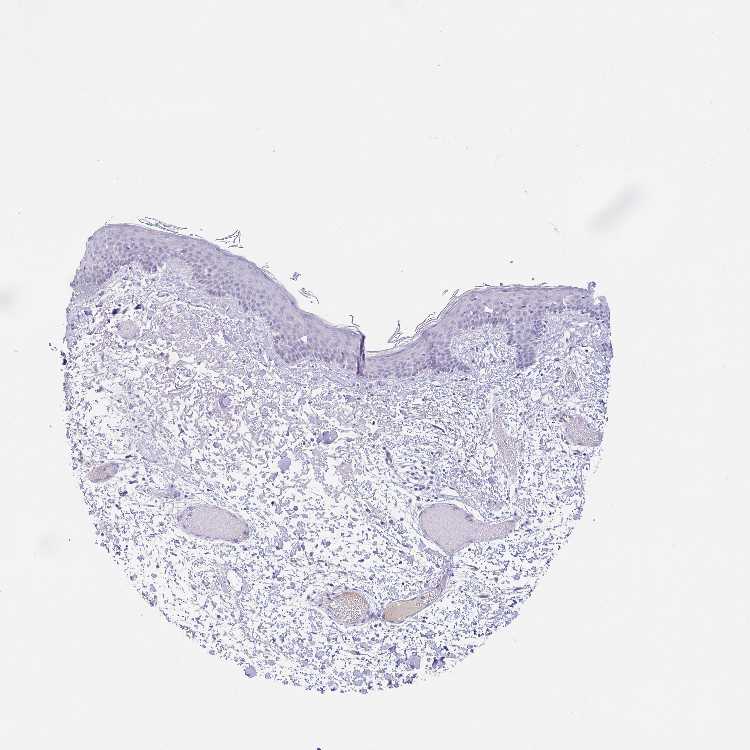

SKIN 1 - Antibody stainingi

Antibody staining in the annotated cell types in the current human tissue is reported as not detected, low, medium, or high, based on conventional immunohistochemistry profiling in selected tissues. This score is based on the combination of the staining intensity and fraction of stained cells.

Each image is clickable and will lead to virtual microscopy that enables deeper exploration of all samples and also displays staining intensity scores, fraction scores and subcellular localization as well as patient and tissue information for each sample.

Antibody HPA028402Antibody HPA043443

Langerhans Not detectedNot detected

Fibroblasts Not detectedNot detected

Keratinocytes Not detectedNot detected

Melanocytes Not detectedNot detected